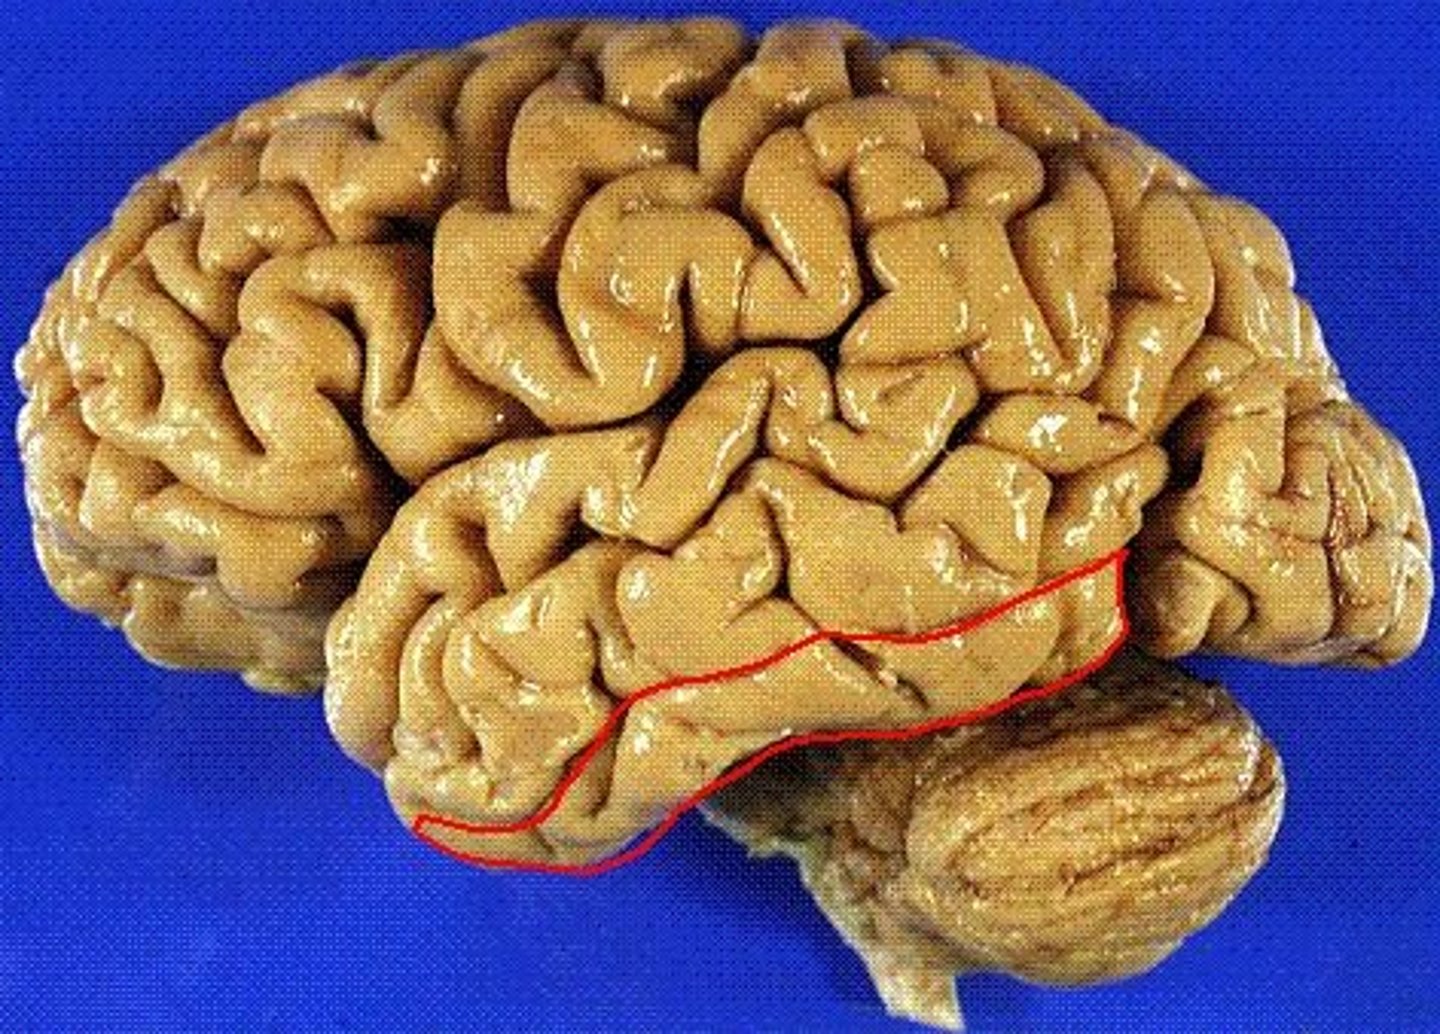

temporal lobe

A part of the brain located behind the ears that is crucial for processing auditory information, memory, emotion, and language. Contains three gyri parallel to the lateral fissure.

inferior temporal gyrus

the temporal lobe gyrus that is located just inferior to the middle temporal gyrus